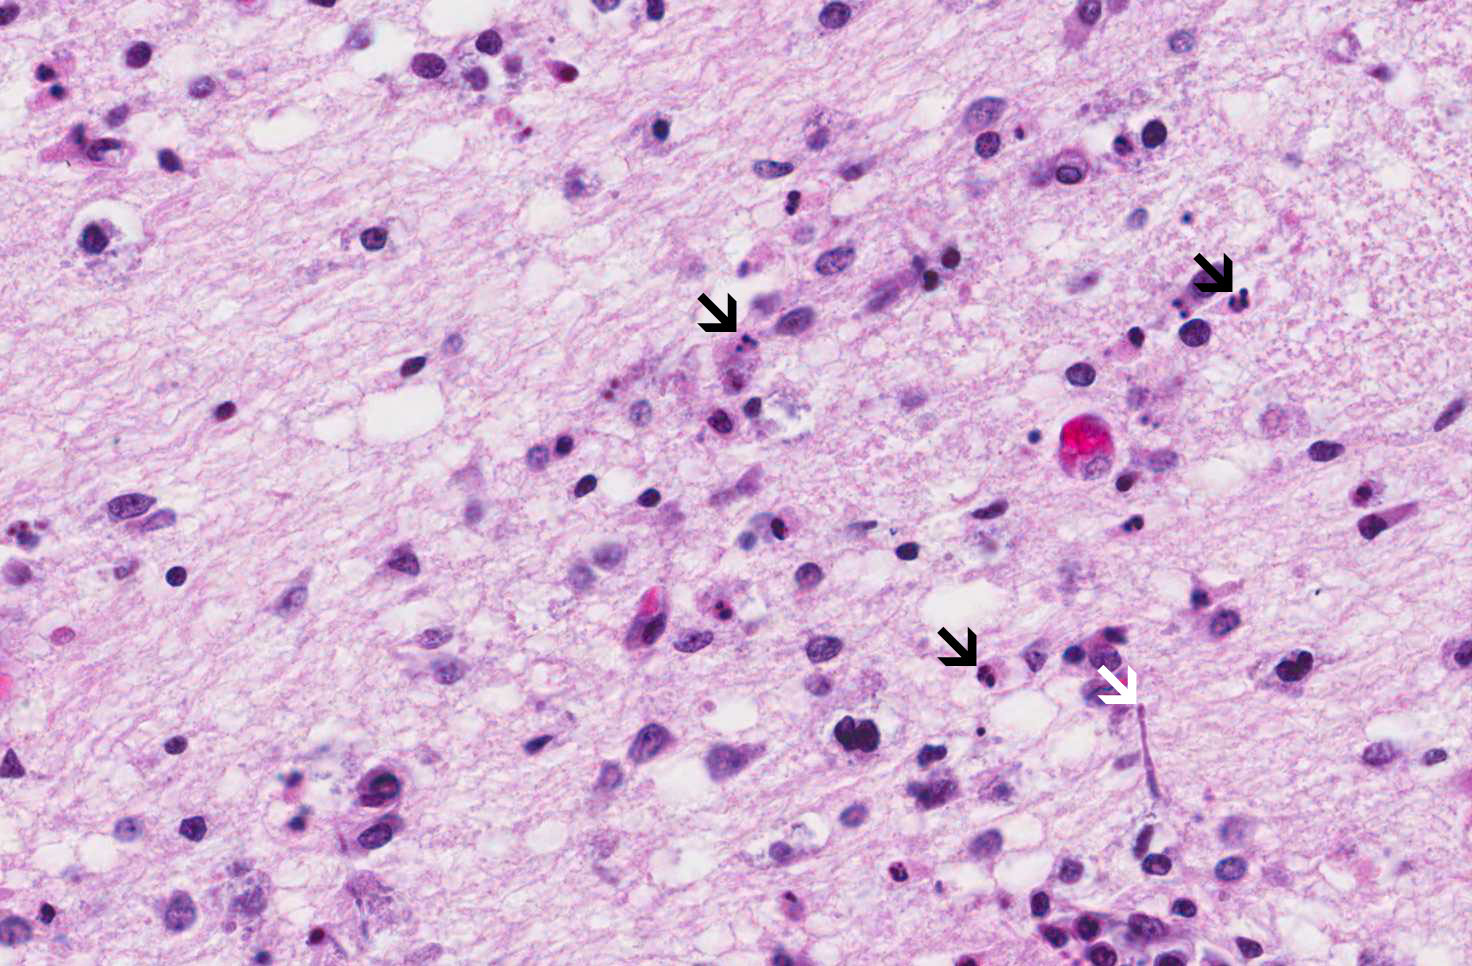

Hematoxylin & eosin

Area 1: Necrotic neurons in premature infants typical present as apoptotic cells (black arrow). Note that scant candida fungal hyphae are present (white arrow)

• In the basis pontis where only small amount of inflammatory cells are present (Area 1), there are many apoptotic cells and scant fungal hyphae. The apoptoic cells are most likely the result of hypoxic/ischemic changes.

• The apoptotic neurons are indicative of hypoxic/ischemic insult. Neuronal necrosis in premature infants typically takes this form and is different from that in the adult where necrotic neurons are elongated, eosinophilic, and loss nuclear details. In this particular case, there are also apoptotic neurons in the subiculum and hippocampus. Together, this form the diagnosis of pontine subiculum necrosis as these apoptotic neurons are far more common to be seen in the pons and the subiculum (adjacent to the hippocampus).